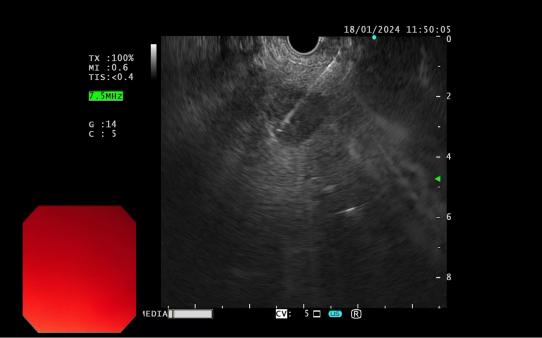

發(fā)現(xiàn)內(nèi)源性低回聲病灶        實(shí)時(shí)超聲引導(dǎo)下對(duì)病灶的細(xì)針穿刺活檢

內(nèi)鏡超聲引導(dǎo)下細(xì)針穿刺抽吸術(shù)(EUS-FNA):治療對(duì)于性質(zhì)不明的胰腺實(shí)性占位性病變;對(duì)于經(jīng)CTMRI或 EUS 等檢查不能確定性質(zhì)的胰腺囊性病變;對(duì)于消化道毗鄰組織中性質(zhì)不明的占位性病變或淋巴結(jié)腫大(如縱隔、上腹部等部位病變);長(zhǎng)徑>2cm需要手術(shù)切除但具有高手術(shù)切除風(fēng)險(xiǎn),或不能切除的消化道上皮下腫瘤的鑒別診斷。